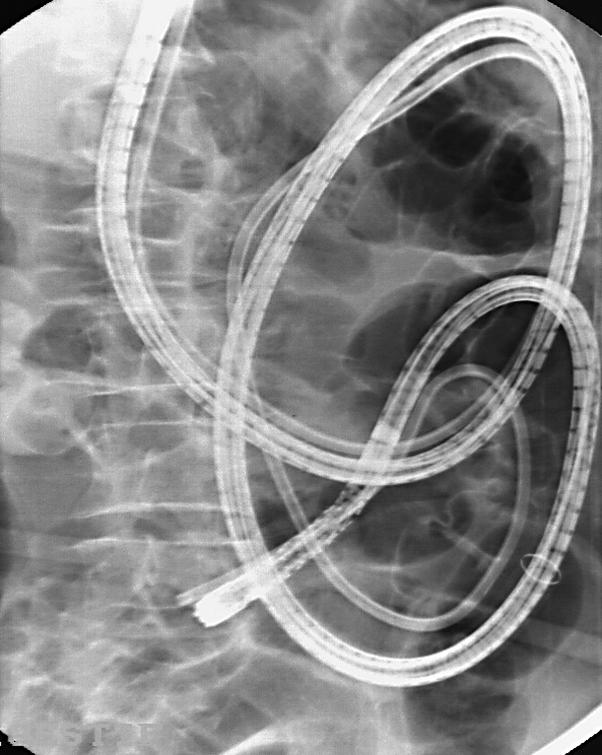

We present the case of a 77-year-old male who was referred for magnetic resonance (MR) enteroclysis because of small bowel subobstruction. To optimise small bowel distention during MR, a nasojejunal balloon catheter was placed to perfuse iso-osmotic water solution into the small bowel. However, after deflation of the balloon, the catheter could not be removed by gentle traction. Subsequently, computed tomography (CT) of the abdomen revealed that the catheter was strangulated deep in the jejunum and traction resulted in painful backward intussusception of the small bowel. In order to avoid surgical intervention, we decided to perform urgent proximal double-balloon enteroscopy to remove the enteroclysis catheter. Under fluoroscopic guidance, the enteroscope was introduced into the jejunum until the tip of the enteroscope reached the tip of the catheter. By straightening the enteroscope, the catheter could then be retracted from the jejunum, using the enteroscope as a guide wire along the catheter. Urgent surgical intervention was avoided and the patient completely recovered the same day.

我们报告一例77岁男性患者,因小肠不全梗阻而接受磁共振(MR)小肠造影检查。为在MR检查期间优化小肠扩张,放置了一根鼻空肠球囊导管,以便向小肠灌注等渗水溶液。然而,球囊放气后,无法通过轻柔牵拉取出导管。随后,腹部计算机断层扫描(CT)显示导管在空肠深部被绞窄,牵拉导致小肠痛苦地向后套叠。为避免手术干预,我们决定紧急进行近端双气囊小肠镜检查以取出小肠造影导管。在荧光镜引导下,将小肠镜插入空肠,直到小肠镜尖端到达导管尖端。通过伸直小肠镜,然后可以将小肠镜作为沿导管的导丝,将导管从空肠中撤回。避免了紧急手术干预,患者于当天完全康复。